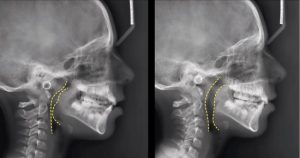

Ключевое отличие заключается в акценте на функции. Традиционная ортодонтия, как правило, фокусируется на перемещении зубов с помощью брекетов и прочих аппаратов, в то время как функциональная ортодонтия стремится к созданию правильного мышечного баланса и оптимальной функции жевания. Это может потребовать использования специальных устройств, способствующих перестройке челюстей, а не только коррекции уже сформированного прикуса.

- Неправильный прикус: Диагноз устанавливается специалистом на основе анализа рентгеновских снимков и визуального осмотра.